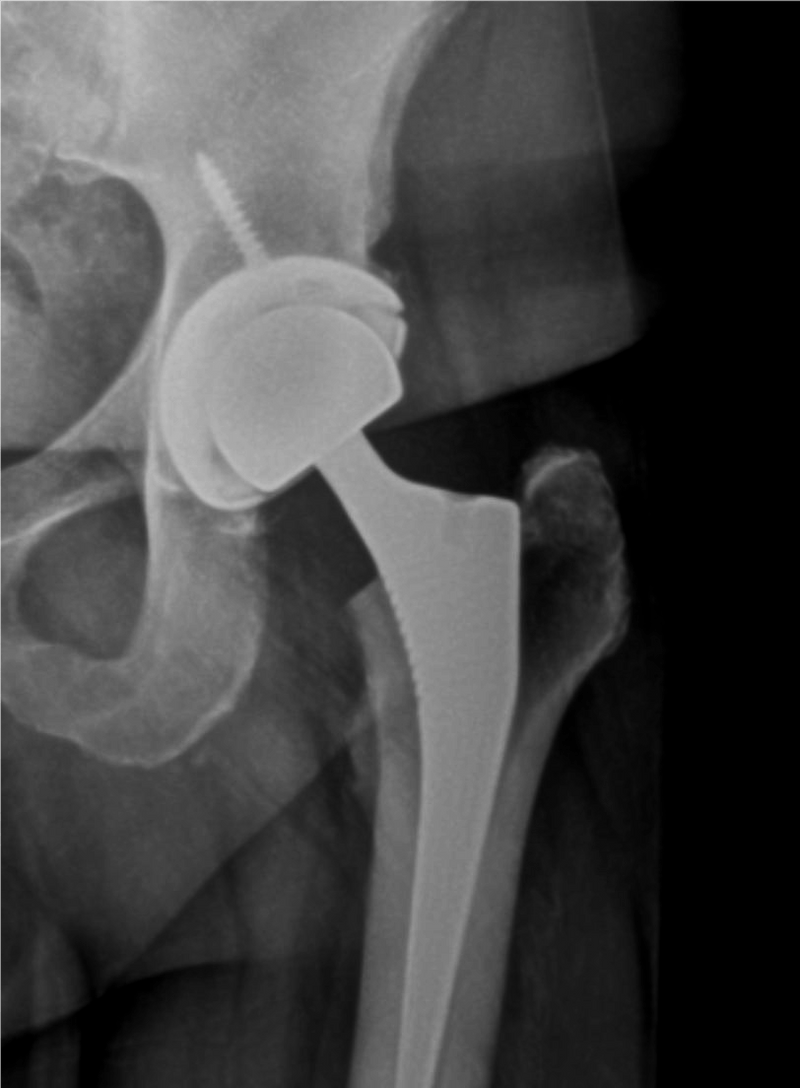

From www.occ-ortho.com

Hip Arthritis And Replacement Orthopedic Centers of Colorado Hip Arthritis Young  Find out what you can do to manage your hip arthritis, from exercise.   learn about the epidemiology, risk factors, clinical presentation, pathology, etiology, classification and radiographic features of.   a comprehensive overview of hip osteoarthritis, a degenerative disease of the hip joint that causes cartilage loss and pain.   research has improved understanding of the causes of hip pain. Hip Arthritis Young.